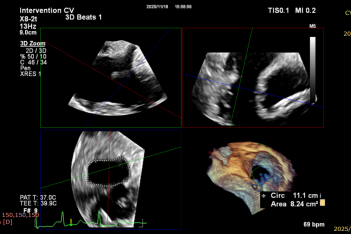

Ultrasound Evaluation: Severe tricuspid insufficiency (mean vena contracta 9mm), with the regurgitation orifice located at the anteroseptal commissure. The mechanism of regurgitation is myxomatous degeneration of the valve leaflets, accompanied by poor leaflet coaptation or reduced coaptation height. The mean diameter of the tricuspid annulus is 37mm. Echocardiographic evaluation confirmed that the anatomical structure is suitable for the K-Clip® system.

CTA Evaluation: Tricuspid annulus circumference: 13.9cm, area: 14.4cm², with low coronary artery risk.

After implanting one 12T K-Clip® device at the commissure of the posterior and septal leaflets of the tricuspid valve and another 12T K-Clip® device at the commissure of the posterior and anterior leaflets, the overall area of the tricuspid annulus was reduced. Tricuspid regurgitation was decreased from severe (4+) preoperatively to moderate (2+), the regurgitation was effectively alleviated, the surgical effect met the expected goals, and the surgery was successfully completed.